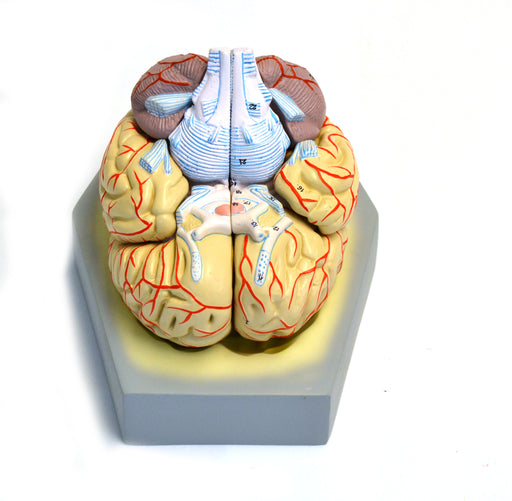

Model, Human Brain, With Arteries, 9 Parts

Life Size 8 part, + base Dissectible Shows Arteries Life size model features arteries of human brain is bisected. Each half can be separated into...

View full detailsAM21AS -